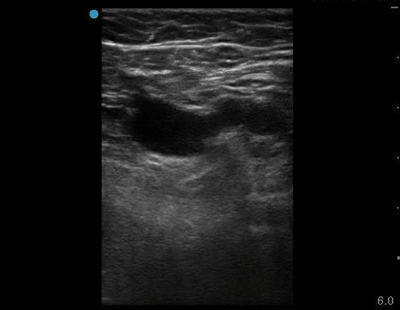

Here we see the anatomy. The point where the saphenous branches from the common femoral vein is the site where blood flow is most turbid. This is very often the site of DVT formation. It is essential to include that point in your study – particularly if you are doing a limited two point compression study. Below is a clip of an ultrasound with a linear probe moving from point A to point B as depicted above. Both left and right are the same clip; the right has labels.